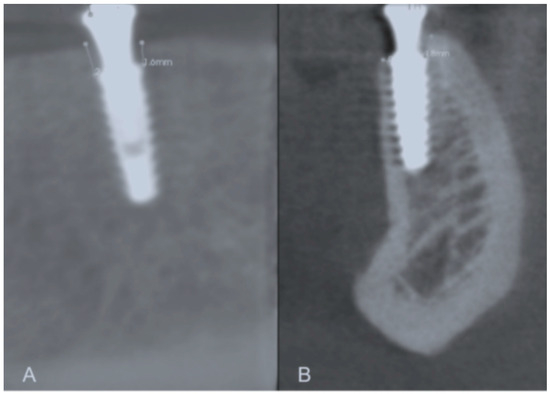

Peri-implant bone level (mm) corresponded to the linear measurement made from the implant platform to the crestal bone (mesial, distal, buccal, and lingually) in the sagittal and coronal slices, recorded every 2 mm (Figure 1). A single research investigator viewed the scans (PHFD) and made all tomographic measurements. Intra-examiner calibration was done using 15 images from patients who received implants for overdenture rehabilitation. The measure was performed twice in 24 h. The reproducibility was calculated as 90%.

Annual bone loss in the two study groups is presented in Table 6. Increased peri-implant bone loss was detected during the first 12 months of implant function compared to during the second year in both test and control groups (p < 0.05). The control group showed higher peri-implant bone loss in the first and second years than the test group (p < 0.05) (Figure 3).

Figure 3. Representative images of the buccal, mesial, lingual, and distal bone level measurements. (A) Mesial and distal bone level measurement; (B) Buccal and lingual bone level measurement.